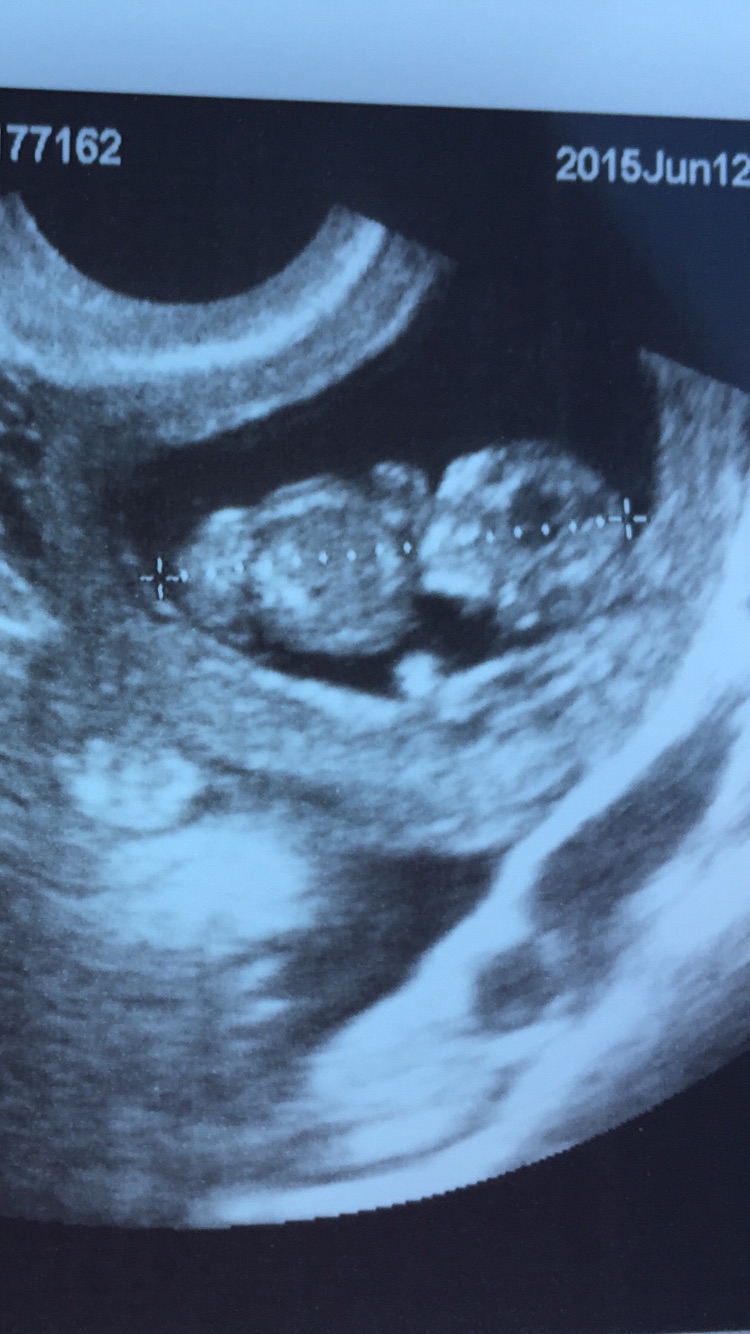

I read it is 97% accurate for singletons and not-tested in twins. In shots of my twins the ones together were at a weird angle so he could image them together and appeared diff than the ones of them separate as far as placenta placement. Does yours? I hope you have one of each that would be great!

My goodness! I have to say you two lovely ladies above this..I find it really tricky! It seems like your baby is at the bottom smack dab right in the middle!!